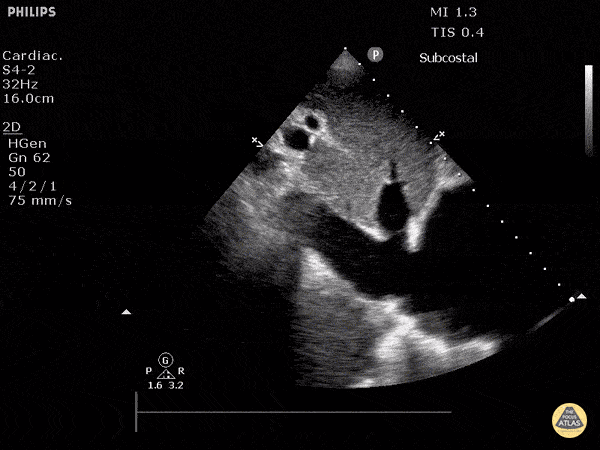

IVC & Abnormal Venous Waveforms - Plethoric Inferior Vena Cava